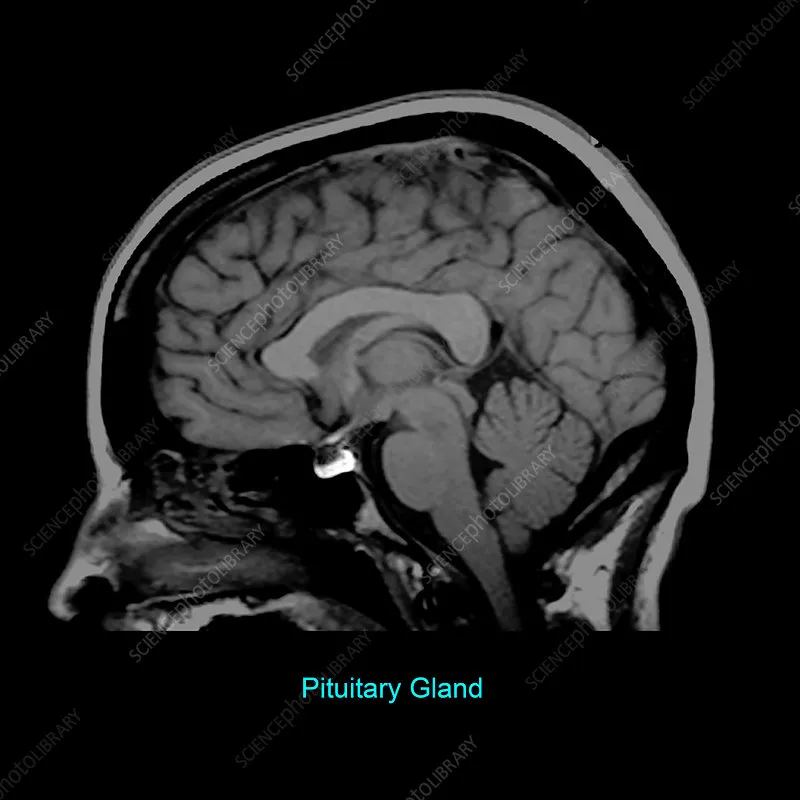

Pituitary Basics - Master Gland Overview

- Location: Sella turcica, sphenoid bone; connected to hypothalamus by infundibulum (stalk).